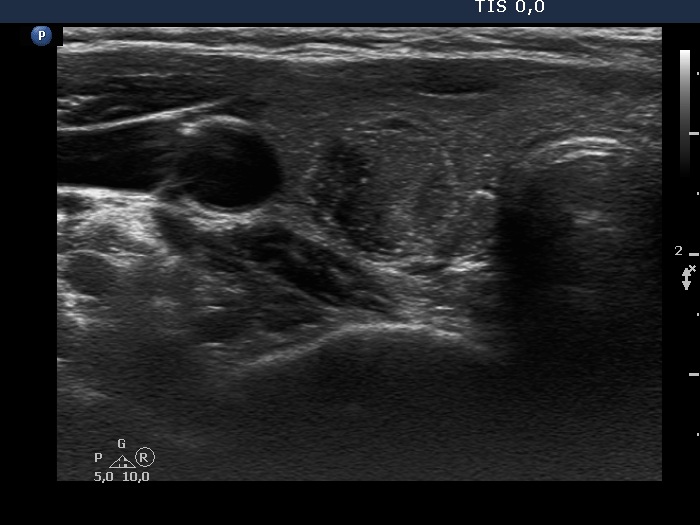

Papillary carcinoma (histological diagnosis) |

This case is less edifying or may be more edifying. Compared with the previous case, the granules here are less bright. Nevertheless, great proportion of them belong to punctate echogenic foci (arrows). It is worth to compare these with non-specific granules (arrowheads). |